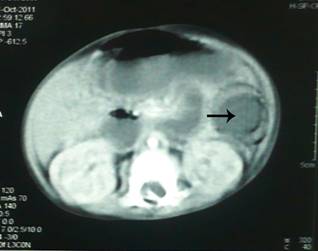

CT scan of abdomen revealed a rounded intra-luminal mass obstructing the bowel lumen

(Fig. 2). Patient had also developed jaundice Liver function tests showed,

Figure

2: CT scan showing a hypo-dense intraluminal bowel mass